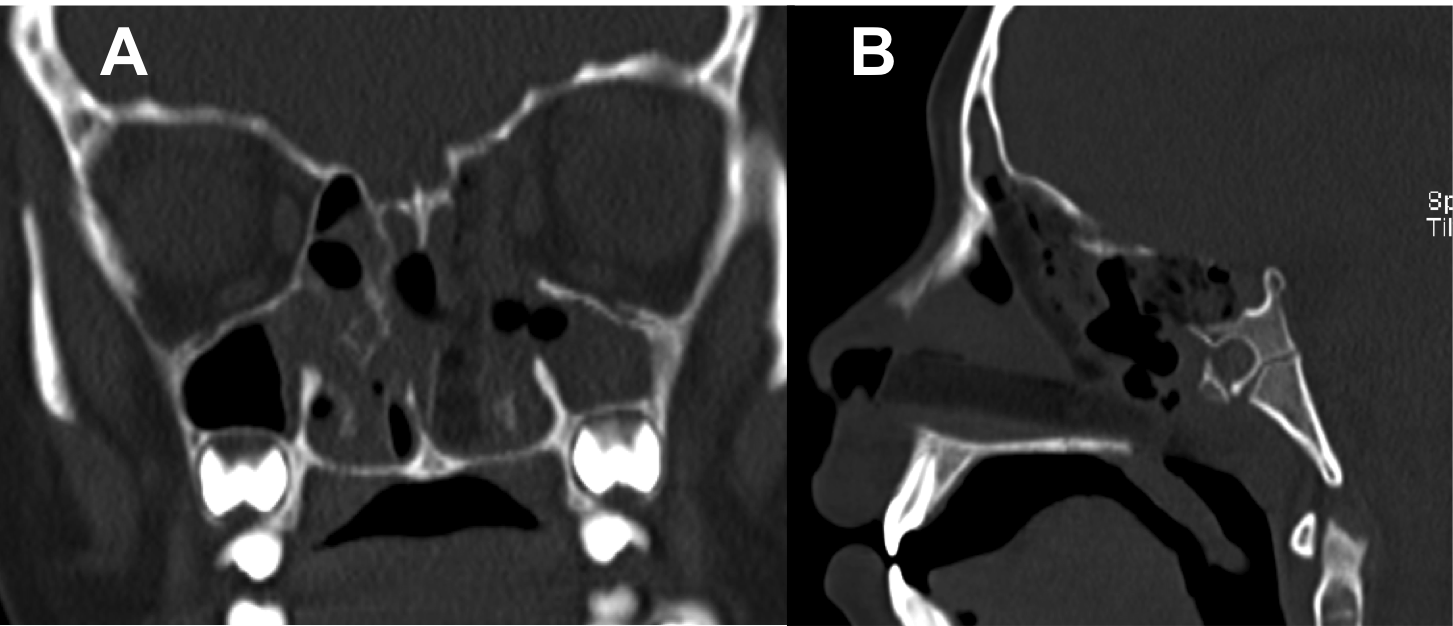

Introducción: La cirugía endoscópica endonasal se ha convertido en una herramienta fundamental para el manejo de patologías que comprometen la base de cráneo. En casos bien seleccionados, estas técnicas permiten resecciones quirúrgicas con una menor morbilidad sin comprometer los principios oncológicos de resección. Con el desarrollo de instrumental especializado, nuevas tecnologías y la experiencia de los cirujanos, la cirugía endoscópica endonasal se usa cada vez más en cirugía de base de cráneo en niños.

Objetivo: presentar una serie de casos de pacientes pediátricos con tumores de base de cráneo manejados con cirugía endoscópica endonasal.

Diseño: Estudio observacional descriptivo de tipo serie de casos. Metodología: se describe la experiencia con pacientes pediátricos llevados a cirugía endoscópica endonasal para manejo de tumores de base de cráneo en el Instituto Nacional de Cancerología entre julio de 2014 y diciembre de 2016.

Resultados: Fueron intervenidos 8 pacientes entre los 2 y 14 años, con una edad promedio de nueve años y un seguimiento promedio de 16 meses. En el 75% se hizo una resección total del tumor. Un paciente requirió una reintervención y un paciente fue sometido a radiocirugía post-operatoria. 1 paciente falleció a pesar de múltiples intervenciones, quimioterapia y radioterapia.

Conclusión: La cirugía endoscópica endonasal para tumores de base de cráneo puede ser utilizada de forma segura en los pacientes pediátricos, es una técnica que en casos bien seleccionados pueden ofrecer excelentes resultados disminuyendo la morbilidad y complicaciones de las técnicas abiertas.